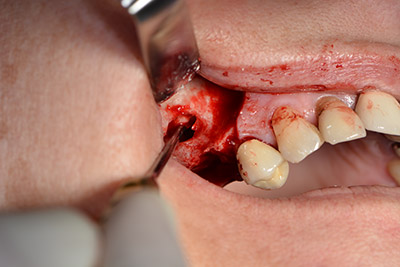

Quindi, abbiamo optato per il rialzo del pavimento sinusale con impianto simultaneo. Implantmed è preimpostato sulla prima posizione per quanto riguarda la fenestrazione buccale della parete del seno mascellare.

La fenestrazione è impostata su 35.000 rpm, mentre la mucosa nasale viene preparata in direzione craniale (da fig. 13 a 14).